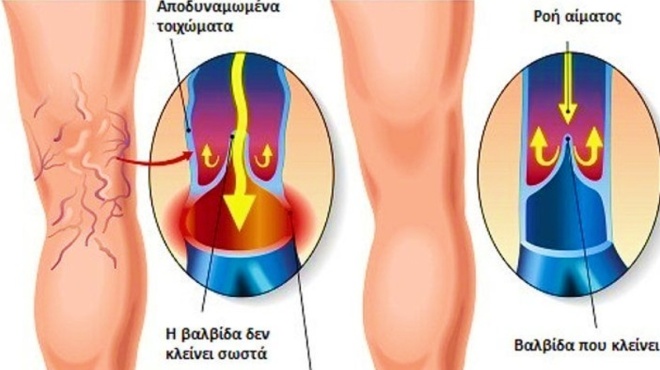

Το πρώτο πράγμα που πρέπει να γνωρίζετε είναι ότι το αίμα φτάνει στα άκρα σας από την καρδιά και μετά ταξιδεύει πίσω μέσω των φλεβών σας. Ωστόσο, για να συμβεί αυτό σωστά, πρέπει να κρατήσουμε τα πόδια μας σε κίνηση. Οι μύες μας λειτουργούν ως ένα είδος αντλίας προκειμένου να καταστεί δυνατή αυτή η διαδικασία.

Αυτή η διαδικασία επιστροφής αίματος στην καρδιά είναι γνωστή ως φλεβική επιστροφή. Όταν κάποιος δεν κινείται για αρκετό διάστημα, διατρέχει τον κίνδυνο ανάπτυξης φλεβικής νόσου. Η πιο συχνή από αυτές είναι οι κιρσοί.